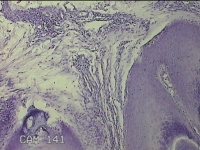

后颈部皮肤结节

性别

男

年龄

45岁

临床诊断

皮肤结节病

发现后颈部皮肤结节半年余。

标本名称

大体所见

灰白粉红色组织1.7x0.9x0.3cm一块,表面带梭形皮肤1.7x0.9cm,皮下见结节1.5x1.1cm一个,切开结节呈实性,切面灰白粉红色,质软。

图1